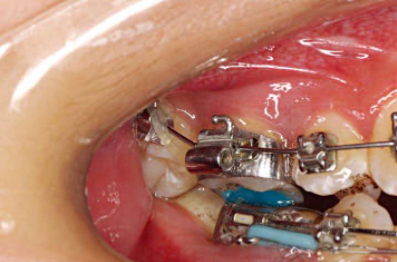

1、上颌带环需要带有口外弓管,下颌带环舌侧选择带蝴蝶翼的。这样方便在后期必要的时候进行磨牙交互牵引(图5,图6)。

下颌粘托槽的时候,如果上颌牙尖咬到了下颌托槽上,可以在上颌磨牙工作尖的工作面做蓝色树脂颌垫(图10)。